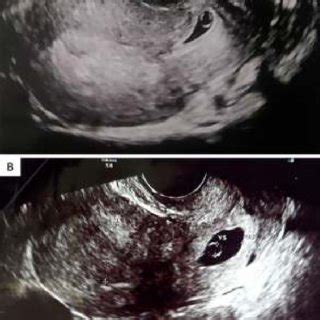

- Ecografía Transvaginal: Es la herramienta principal. Permite visualizar el saco gestacional y determinar la presencia o ausencia de un embrión y su latido cardíaco. Un saco gestacional mayor de 2 cm sin embrión visible es un indicador importante.

Es importante destacar que, a pesar de la ausencia de embrión, la prueba de embarazo puede dar positivo debido a que las células del saco gestacional continúan produciendo hCG.